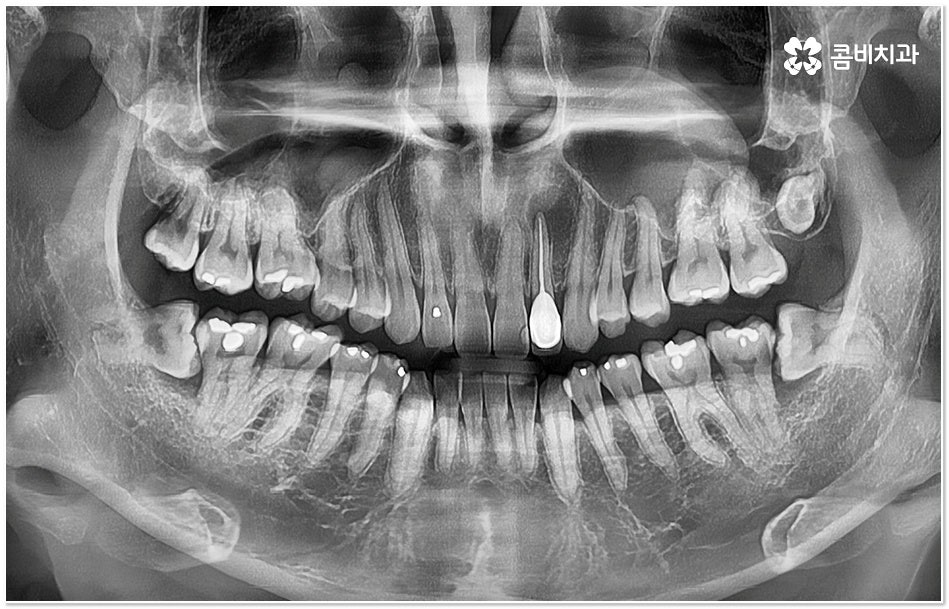

사랑니와 어금니 인접면에 치아 사이 충치 가 발생할 경우 육안으로도 보기 힘들 뿐 아니라 엑스레이를 찍었을 때에도 쉽게 발견하기 힘들 수 있기 때문에 초기에 알아차리지 못하고 치료 시기를 놓치는 경우가 종종 생기며 손상 정도가 많이 심각하거나 위치상 사랑니 발치 후에도 뿌리 끝 염증이 매우 심하거나 치아 사이 충치 로 손상이 심해 치료가 불가능한 케이스의 경우 불가피하게 어금니까지 발치를 해야 할 수 있으므로 이와 같은 상황에 이르지 않도록 평상시에 정기 검진을 꼬박꼬박 받아주는 것이 조기 대처 및 예방 등에 있어 여러 모로 유리하다고 할 수 있습니다.

특히 사랑니가 나오는 시기인 10대 후반부터 20대 초반에 3D CT와 같은 정밀 진단 장비를 통해 사랑니 검진을 한 번 꼼꼼하게 받아보시고 구강 상태를 세세하게 파악한 뒤 비스듬하게 누워있거나 잇몸뼈 속에 매복이 되어 앞 어금니 및 전체 구강 건강에 좋지 않은 영향을 지속적으로 줄 수 있는 상황이라고 판단이 된다면 발치 계획을 세워서 미리 뽑아주는 것도 좋을 거예요.